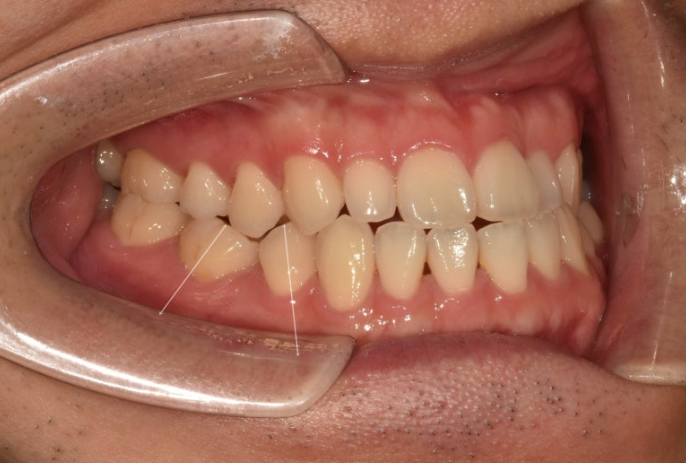

치료시작 1년 5개월 차 치료를 마무리 했습니다.

25.06

중심선은 잘 맞고 한쪽 어금니 반대교합은 별도의 악궁확장 없이 좋아졌습니다.

결손된 작은어금니 쪽으로 쓰러져 있던 큰어금니는 잘 세워졌습니다.

교합은 좋습니다.

남겨둔 아래 사랑니도 잘 교합되고 있습니다.